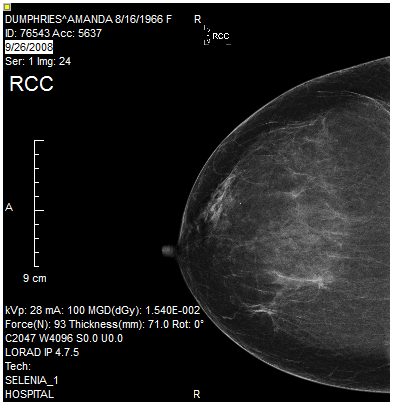

The Rotate Image 90 Degrees Clockwise tool will rotate an image 90 degrees to the right. The following example illustrates an image before and after the Rotate Image 90 Degrees Clockwise tool is applied.

| Before | After |

|---|---|

![]() | ![]() |